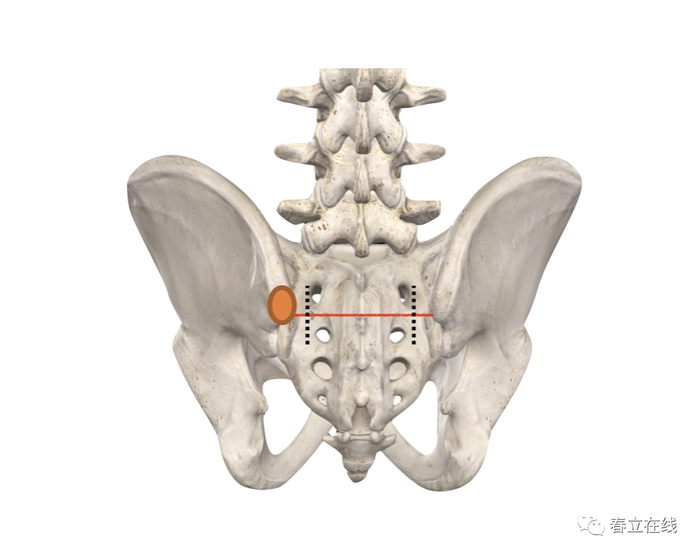

医生需要对侧辨识进钉点。解剖学标志是髂骨后上嵴。

透视确认合适的置钉路径,将C臂机放置在进钉点上方,然后将其向尾端倾斜20—30度。水平倾斜40—50度;对准髂前下棘。此机位下,可在AP位透视上观察到髂骨泪滴。

使用开路器、探针探查。选择的路径方向为水平方向倾斜40—50度,同时向尾端倾斜20—30度,该方向可因骨盆的倾斜和腰椎的前凸的改变而改变。

选择合适螺钉直径和长度,如下图

使用上钉器连接螺钉,对准髂前下棘方向,并在坐骨切迹上方植入螺钉,在完全植入螺钉之前,移除导针引导以免折弯或损坏。